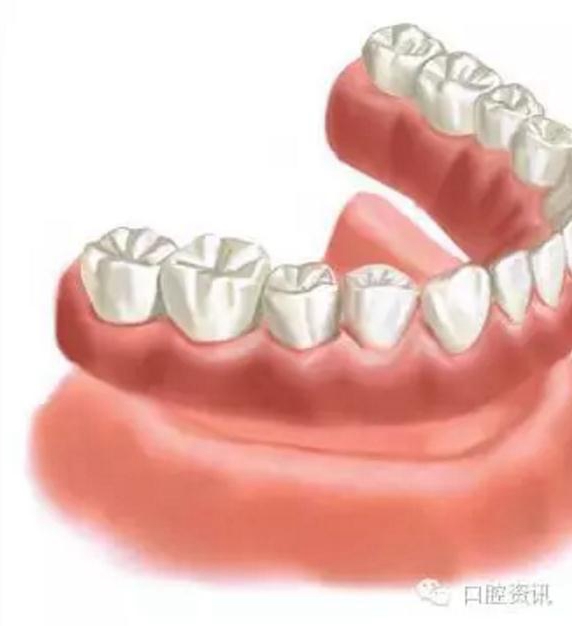

圖8. 可摘局部義齒

4 . 全口義齒

傳統(tǒng)的全口義齒利用牙床和黏膜提供固位力。而當(dāng)天然牙缺失后, 牙槽骨會逐漸吸收, 這會影響義齒的穩(wěn)定度, 進(jìn)一步會影響您的咀嚼功能和舒適感。義齒可能需要反復(fù)調(diào)改才能達(dá)到滿意的效果。這種情形下, 通過種植體支持全口義齒, 可以有效地提高義齒的固位力。